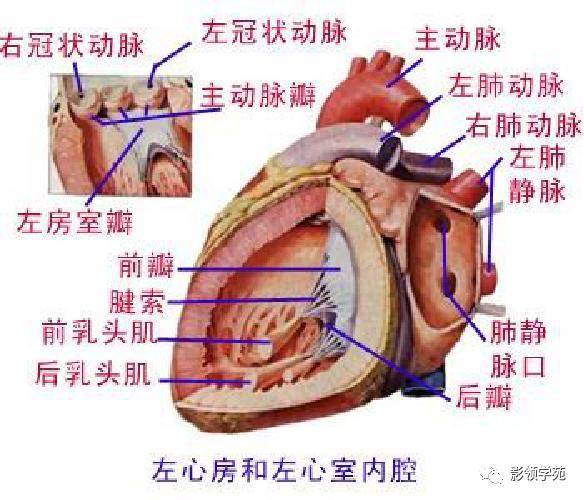

心血管系统

心血管系统